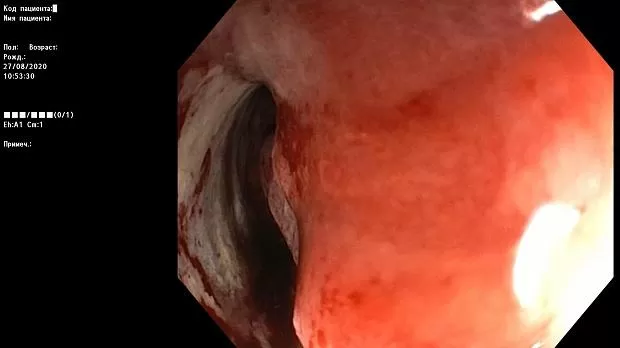

Краткое описание эндоскопической картины.

В проксимальной части сигмовидной кишки имеется асимметричное циркулярное сужение за счет плотной бугристой ткани, с признаками ригидности, структура поверхности и сосуды не визуализируются.

Просвет опухолевого канала 1 см, определенная протяженность — около 10 см. Патогистологическое исследование № 1455-62 от 28.08.2020 г.